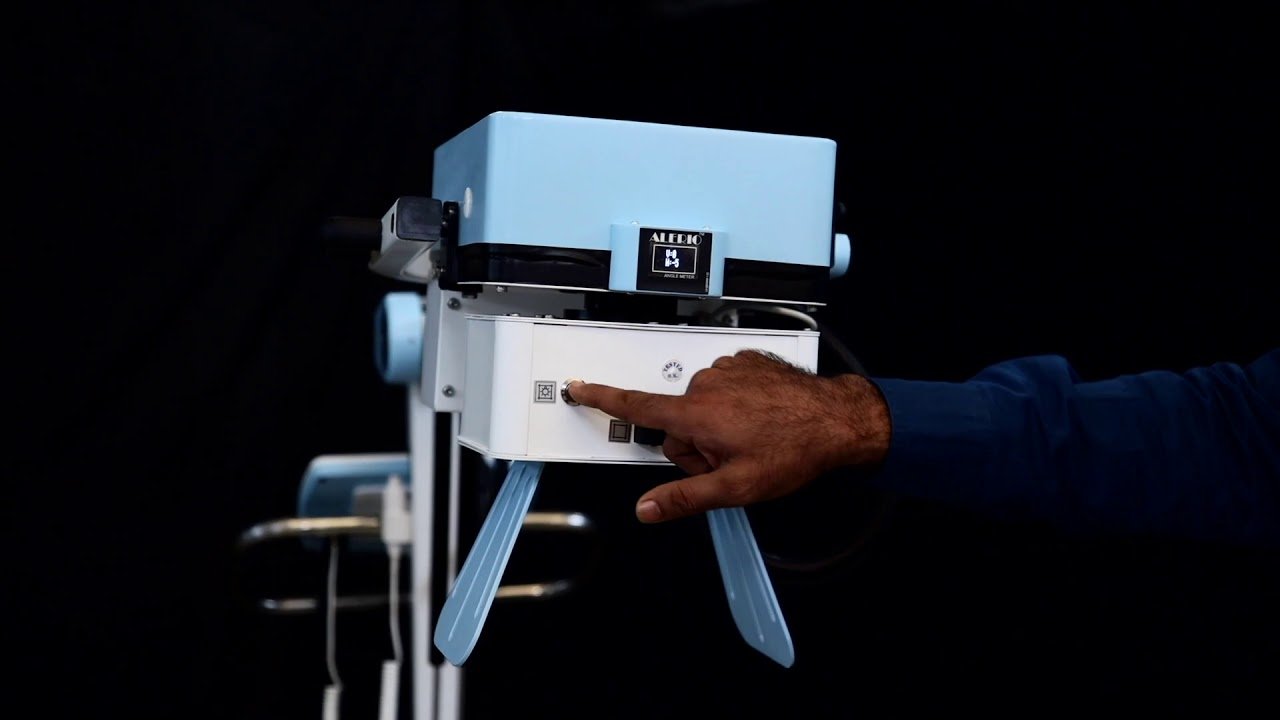

.jpg)

.jpg)

ALERIO SMART 5000

$325